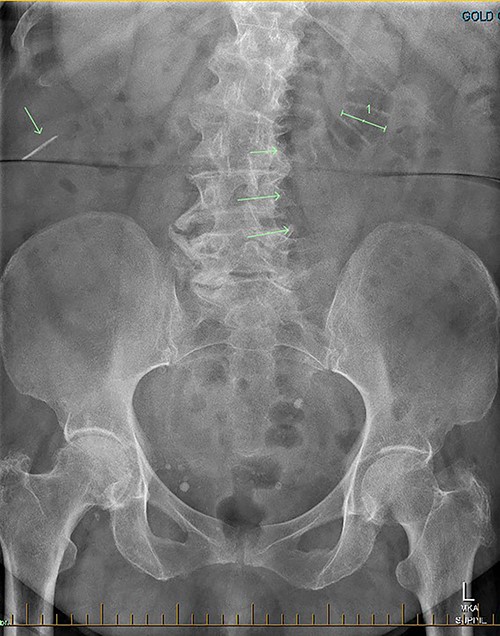

Patient SC is a 72-year-old lady who presented with urosepsis secondary to a left-sided distal ureteric renal stone. Her medical history includes ischemic heart disease, chronic pulmonary obstructive airway disease, type 2 diabetes mellitus, Parkinson’s disease and a previous open cholecystectomy. She was admitted to the intensive care unit and a left-sided nephrostomy tube was inserted. Initial CT imaging incidentally identified a ‘bread clip’-shaped FB in the distal jejeunum (Figs 1 and 2). There was no evidence of obstruction nor perforation. Abdominal X-rays failed to show the presence of a FB.

Secondly, as shown in the three cases, unless the BC is calcified, abdominal plain films are not a reliable method of tracking nor diagnosing BC ingestion [9–13]. CT is more sensitive, with a sensitivity rate of 67%, but is not consistently reliable on its own [6, 7]. Reconstructed 3D imaging is effective in identifying BCs. Most BCs are made of low-density polystyrene, a type of versatile solid plastic, which are not readily identified on plain film imaging [14, 15]. This non-degradable plastic means that it is usually only a matter of time before a patient develops a complication.